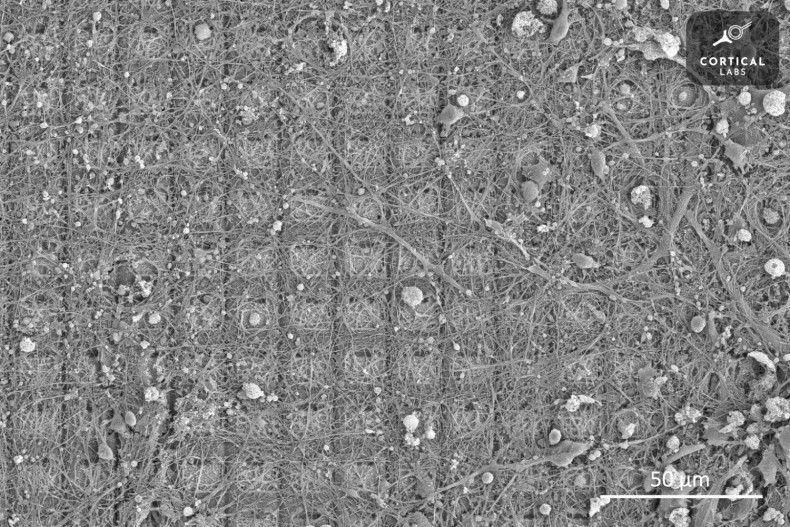

Brain cells in dish learn to play video game

Life, Issam Ahmed of AFP, Published on 19/10/2022

» ISLAMABAD: Neuroscientists have shown that lab-grown brain cells can learn to play the classic video game Pong, and could be capable of "intelligent and sentient behaviour".